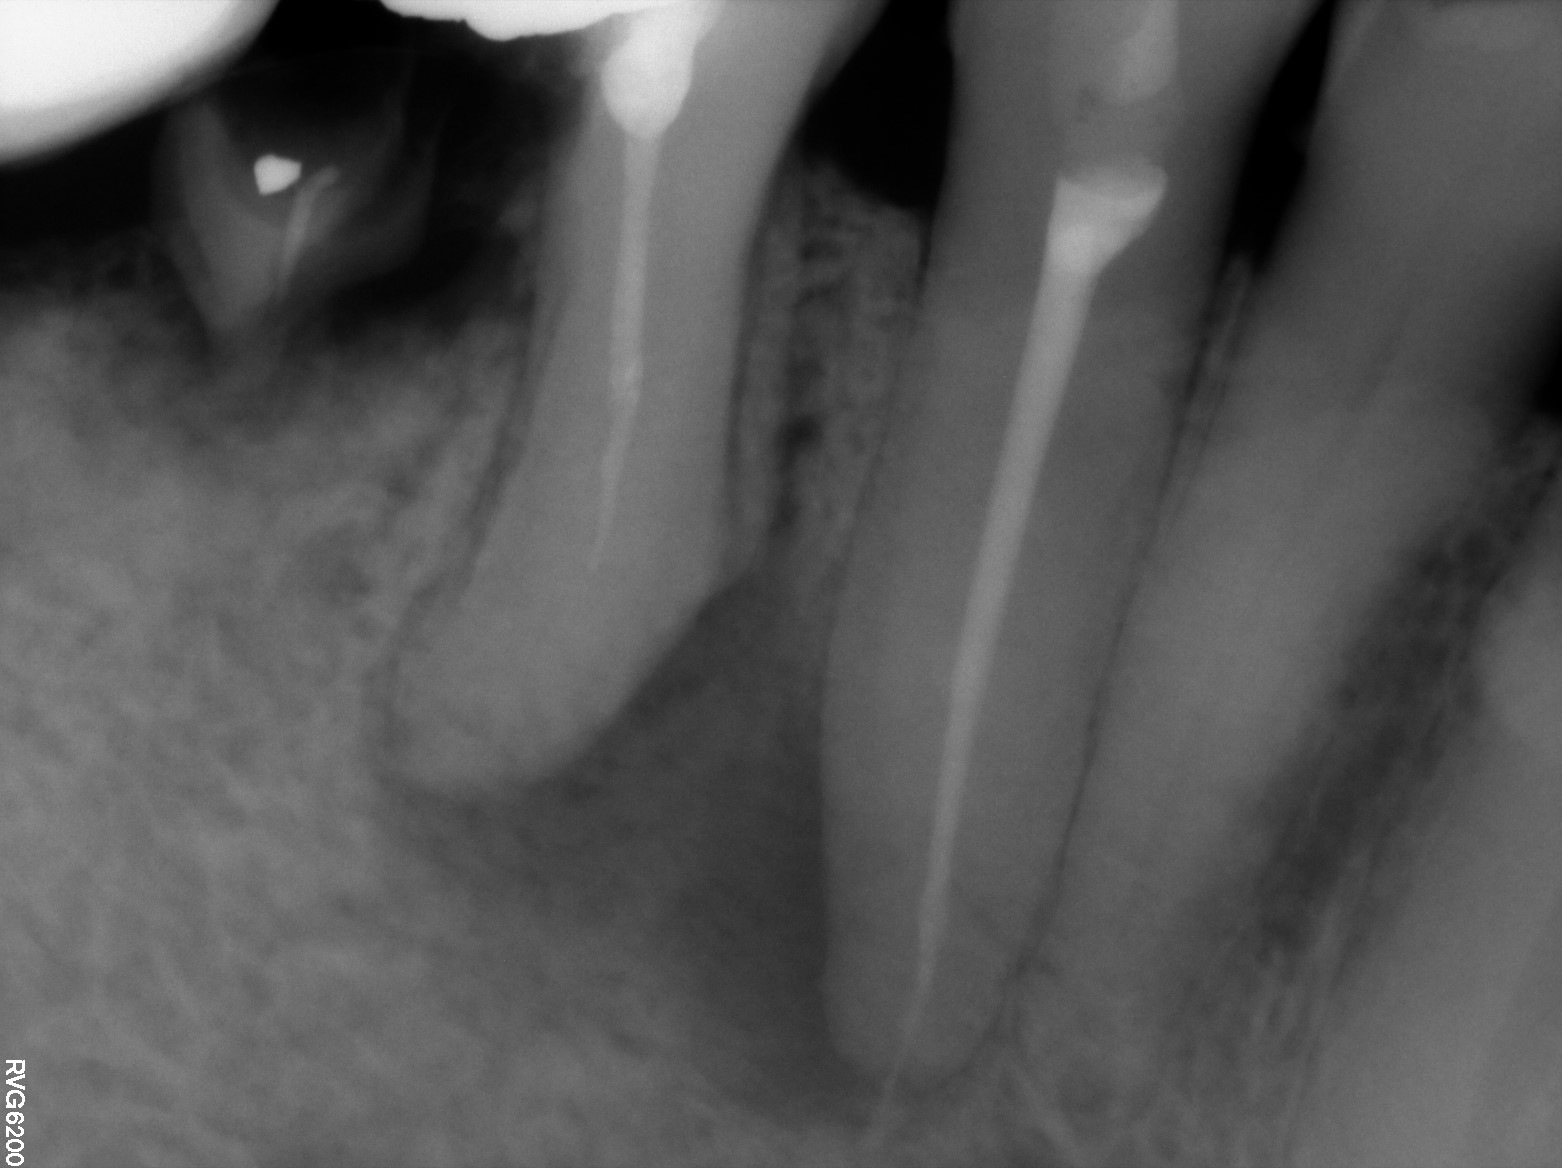

Endodontic cases

These cases highlight a range of endodontic diagnoses and treatments managed within a specialist setting. They provide insight into the assessment, treatment planning, and evidence-based management of complex cases, reflecting a systematic approach focused on preserving natural dentition and supporting referring clinicians through clear clinical rationale and outcomes.